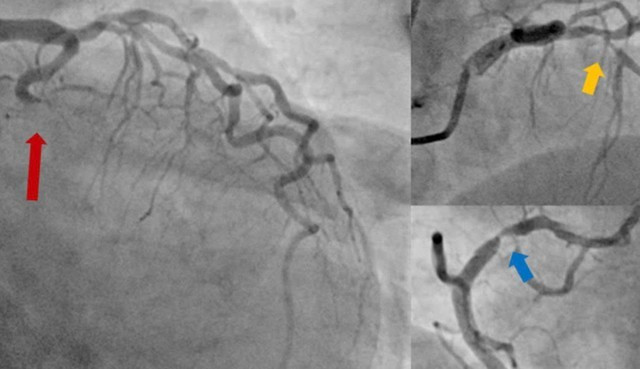

Hình ảnh chụp động mạch vành cho thấy tắc hoàn toàn động mạch mũ (mũi tên đỏ), hẹp nặng cả động mạch liên thất trước (mũi tên vàng) và động mạch vành phải (mũi tên xanh).

Người bệnh sau đó được đưa đến phòng DSA để được chụp động mạch vành cấp cứu. Kết quả chụp mạch vành cho thấy tắc hoàn toàn động mạch mũ, hẹp nặng động mạch liên thất trước và vành phải.

BS.CKI. Nguyễn Thanh Bình, Phó Trưởng khoa Nội Tim mạch nhận định: “Đây là trường hợp ngưng tim sau nhồi máu cơ tim, với thủ phạm là tắc hoàn toàn động mạch mũ, đồng thời hẹp nặng cả hai nhánh động mạch vành còn lại. Việc can thiệp tái thông hoàn toàn cả động mạch thủ phạm và hai động mạch hẹp nặng là phù hợp với các khuyến cáo hiện hành và sẽ giúp khả năng cứu được người bệnh cao hơn”.